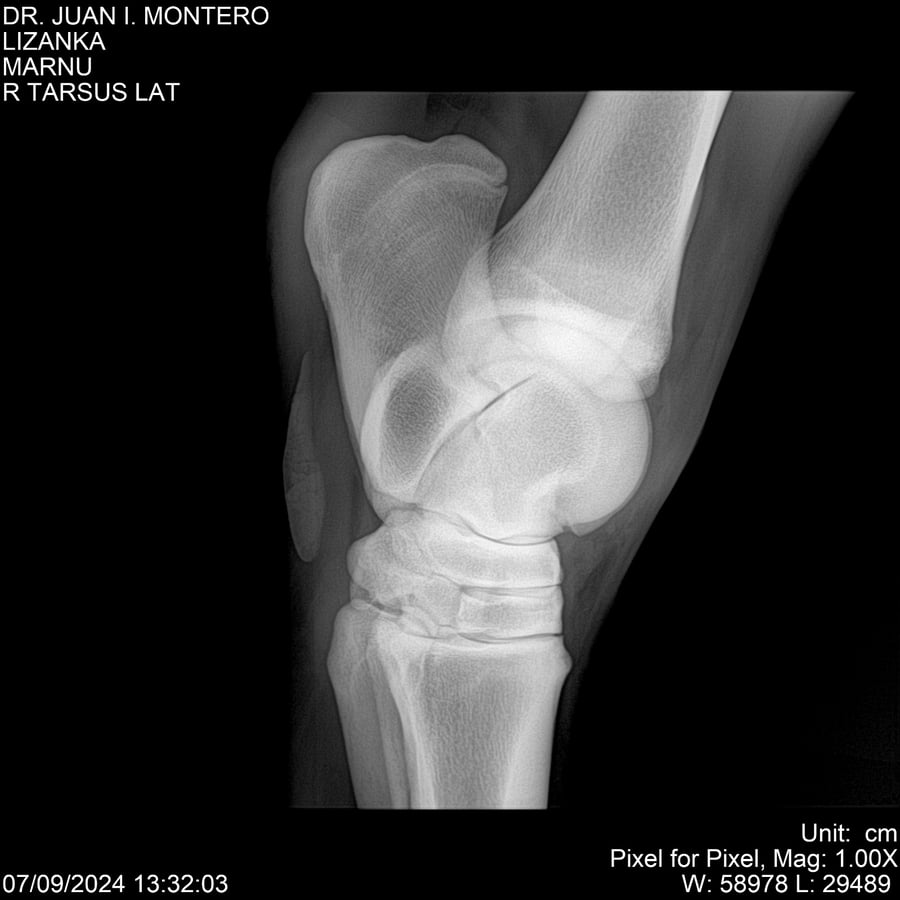

LOTE 18, LIZANKA Lote Anterior Volver al remate Lote Siguiente Ficha Contacto Montevideo - Ficha del Lote Identificador: #282512 Categoría: Yeguarizos Montevideo - 62 Visualizaciones ClicData Contacto Empresa: Abelenda N. R., Walter Hugo Nombre*: Teléfono* : E-mail* : Mensaje Enviar Registrese gratis Este contenido Exclusivo está disponible sólo para usuarios registrados Ingresar